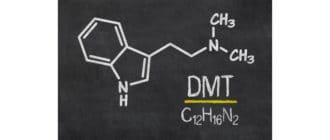

DMT(N、N-ジメチルトリプタミン)は、多くの植物および動物に自然に生じる幻覚誘発性トリプタミン薬である。激しいサイケデリックな経験のため、「精神分子」とも呼ばれています。 LSDや魔法のキノコのような他のサイケデリッ […]